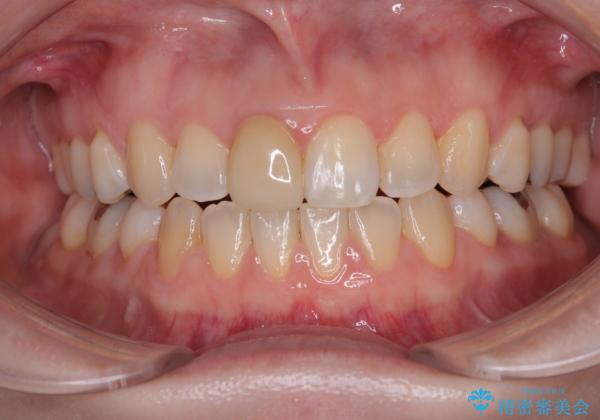

【モニター】後戻りでできた隙間 ワイヤー装置での再矯正

- 学生時代に行った抜歯矯正の後戻りで、隙間ができてしまったことを気にして来院された患者様です。

舌の突出癖が非常に強く、その影響で隙間ができてしまったので、舌のトレーニングをしっかりと行っていただきました。

上顎歯列は歯の移動量が少なかったため、セラミッククラウンは装置を装着せずに治療を終えることができました。